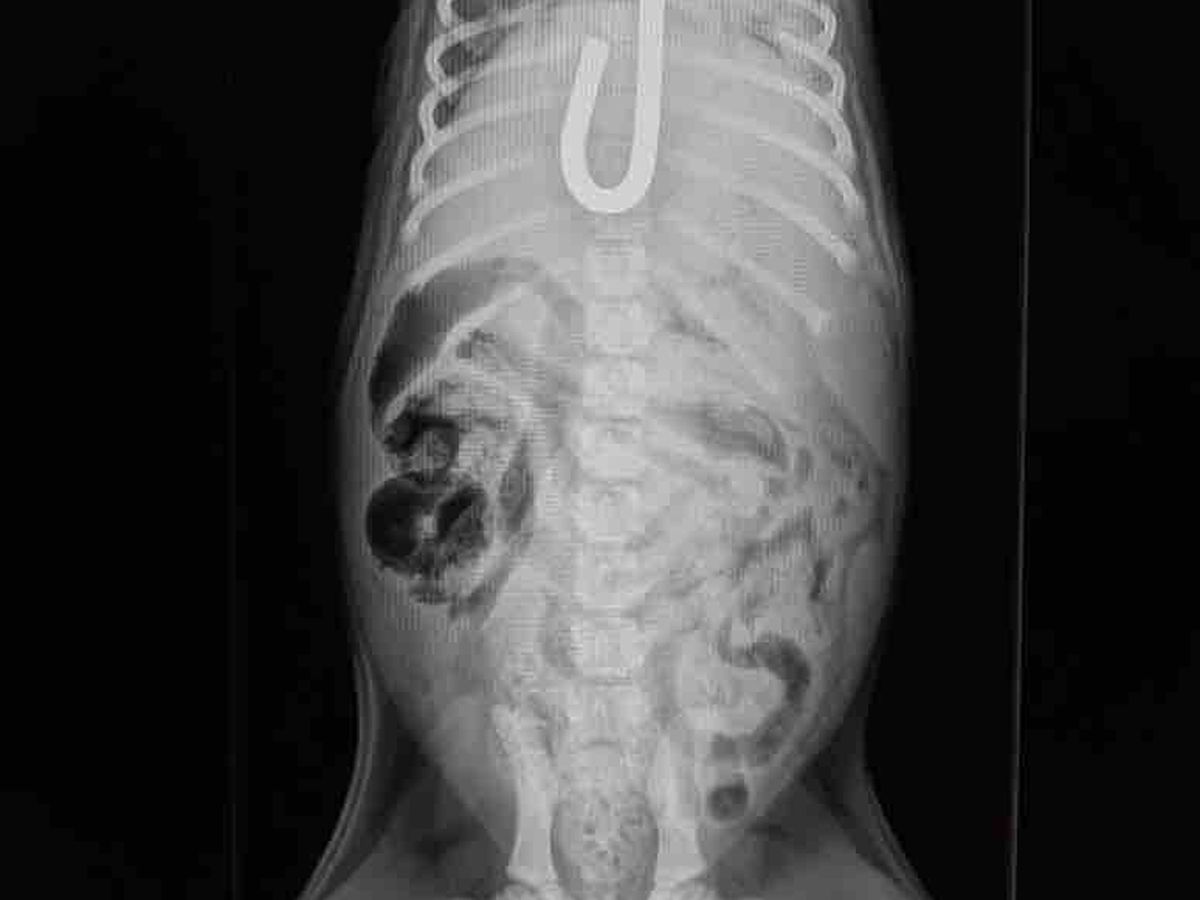

Yesterday morning a vet tech from Tampa called my cell phone and was desperately trying to find help for a young puppy who had impaled herself on a metal rod that went into her mouth down her throat and into her stomach. She had surgery to remove the rod however she has developed additional problems and needs emergency surgery. Canela has Intussusception is when a part of the intestine telescopes or folds in on itself. Estimate is $7000-$9000. I am going to have to close intake while we try to raise funds for the poor puppy. Canela needs your help and prayers.